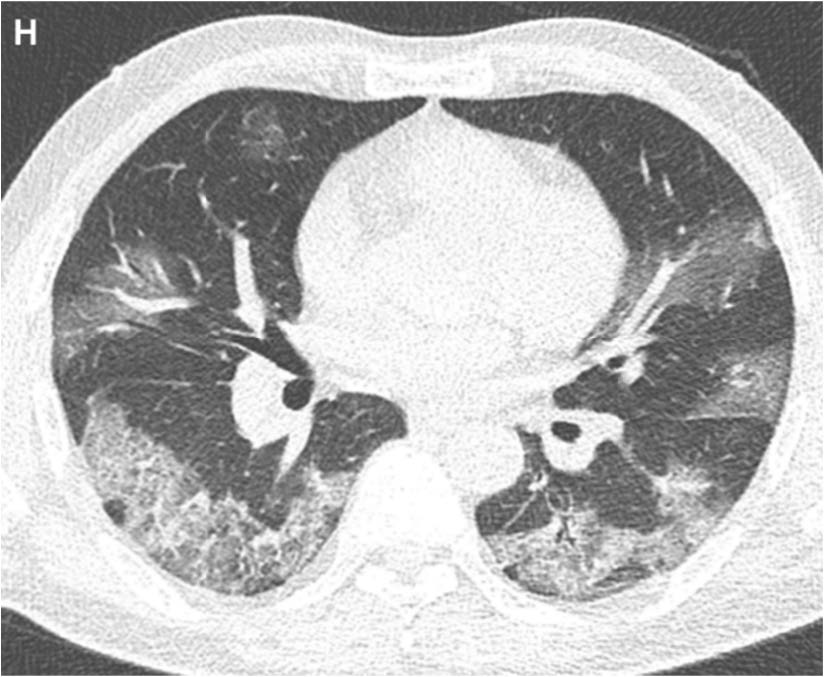

What is your diagnosis?